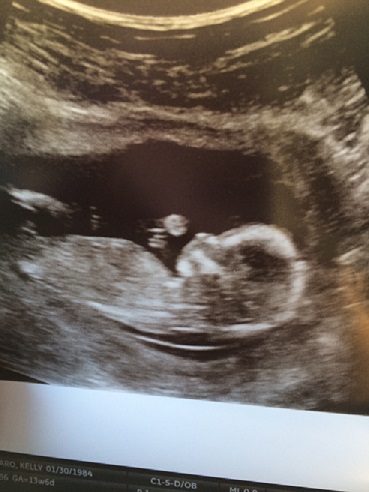

We kind of had a gap in pictures between weeks 10 and 20. Mostly because we didn’t want to jinx ourselves and create the entire string of photos that we wouldn’t want to look at if something had happened. So we took a break from that. Kelly was feeling much better and showing. No more morning sickness, she started to get some of her energy back and our 20 week Ultrasound revealed 10 little fingers, 10 little toes, 2 arms, 2 legs, 2 little feet, a whole bunch of other baby parts, a smirking face, and we are assuming a penis or the absence of a penis. We aren’t finding out the sex so we kept that a surprise. No sign of Down Syndrome or any type of birth defect, but Kelly still needed to complete the blood test portion of the Sequential Screening to rule out Down Syndrome and other issues, routine stuff really. All eventually came back normal and we were on our way. Here is the Kelly Belly (I’m calling it that from now on) at 20 weeks: